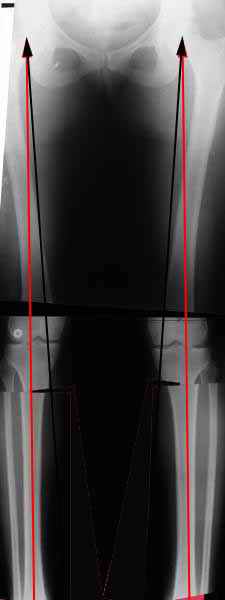

Судя по снимку у девушки имеется внутренняя установка надколенников...

Как у нее с торсионным статусом? Бедро? Голень? КТ? Торсиометры? А то, куда будут

смотреть надколенники после вашей коррекции - тоже существенный

косметический момент. Или не так?

Вот, с учетом и без учета, и на разных уровнях...

Из приведнной схемы не совсеим понял что означают разноцветные линии.

И зачем латерализация периферического фрагмента. Я всегда делаю медиализацию. См схему. И для данного случая медиализация подходит как нельзя лучше.

a> Из приведнной схемы не совсеим понял что означают разноцветные линии.

Черные - это нынешняя механическая ось. Красные - это планируемая правильная ось.

a> И зачем латерализация периферического фрагмента.

;-) Читайте Палея. Стр. 114-115.

a> Я всегда делаю медиализацию. См схему. И для данного случая

Медиализация - это чисто эстетический прием, как я понимаю. Поскольку если делать остеотомию ниже вершины деформации, для восстановления оси надо делать смещение по ширине, в данном случае как раз латерализацию.